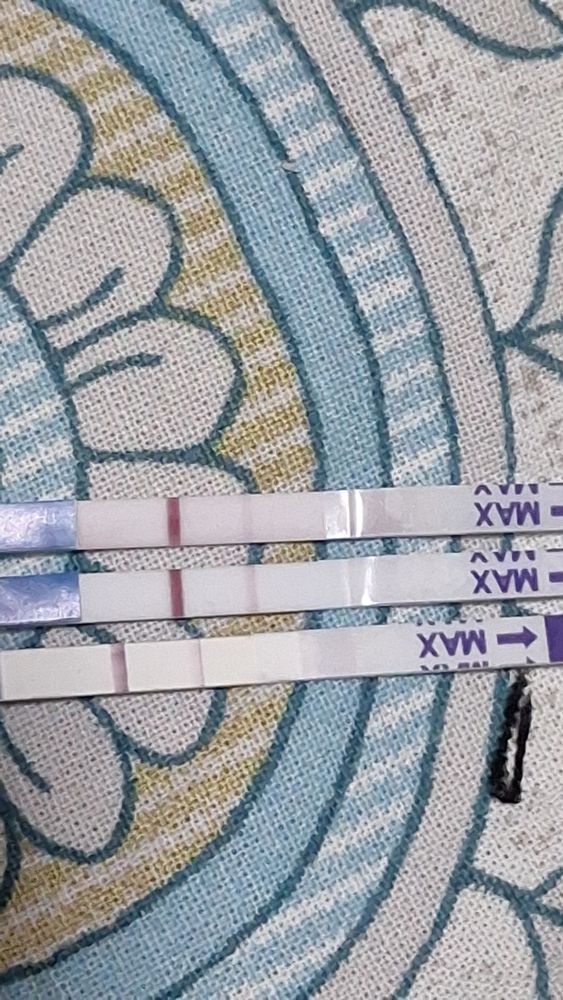

Здравствуйте. У меня такая ситуация. 3 день задержки месячных , с мужем планировали беременность (вторая уже) , тесты положительные , так же делала электронный показал беременность 1-2 недели , пришла сегодня на узи ничего не нашли. Если посчитать срок от первого дня последних месячных то уже 5 недель 0 дней. Почему так? Узист сказала сдавать кровь на хгч каждые 2 дня и придти через 10 дней на узи. Вот переживаю вдруг внематочная , или замершая.